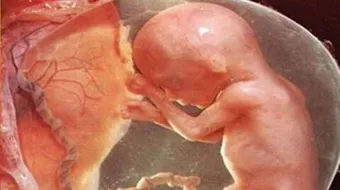

وضع رأس الجنين في الشهر السادس

الجنين في الشهر السادس غالباً ما يكون كثير التقلب وبالتالي يكون رأسه غير مستقر في مكان محدد، ومن الممكن أن يصبح رأس الجنين في أسفل بطن أمه، وهذا الوضع ليس مقلقاً ولكن يجب على الأم بهذه الحالة هو أن تهتم براحتها، وتتجنب القيام بأي مجهود.

تطوّر نمو الجنين في الشهر السادس

الأسبوع الثاني والعشرون

- يبلغ وزن الجنين حوالي أربعمئة وخمسين غراماً، وطوله ثمانية وعشرين سنتمتراً.

- تتكوّن شفاه الجنين، ومعالم وجهه تصبح أكثر وضوحاً.

- تتكوّن أسنانه وأنيابه تحت اللثة، وتنمو خارج اللثة بعد الولادة بفترة.

- لون قزحية عينه لم يتشكّل بعد، ولكنّ عينيه تكونتا.

- قلبه يضخ دماً بمعدل أربعة أميال في الساعة.

- تتشكّل التجاعيد بكثرة على جلده، ولكن هذه التجاعيد ستزول عندما تبدأ الدهون بالتراكم على جسمه.

الأسبوع الثالث والعشرون

- يصبح وزن الجنين حوالي خمسمئة وخمسين غراماً، وهذه الزيادة في الوزن ناتجة عن تراكم الدهون، وتشكّل العضلات، وطوله يبلغ تسعة وعشرين سنتمتراً.

- تنمو وتتطوّر أذنه الداخلية، فيصبح قادراً على السمع والاستجابة للأصوات.

الأسبوع الرابع والعشرون

- يبلع وزن الجنين في هذا الأسبوع ستمئة غرام، وطوله يصل إلى ثلاثين سنتمتراً.

- مادة الميلانين تبدأ بالظهور وبالتالي تقلّ شفافية الجلد.

- تتشكّل الحويصلات في رئتاه، وكذلك تعمل على إفراز مادة السيرفاكتنت التي تعمل على تمديد الحويصلات، وبالتالي سهولة التنفس بعد الولادة.

الأسبوع الخامس والعشرون

- بلغ وزن الجنين ستمئة وتسعون غراماً، وطوله حوالي أربعة وثلاثين سنتمتراً.

- يكون قادراً على التمييز بين الأصوات بشكل أكبر.

- حلمات الثدي تبدأ بالتشكل.

الأسبوع السادس والعشرون

- وزن الطفل بلغ السبعمئة وستون غراماً، وطوله خمسة وثلاثون سنتمتراً.

- يقفز الجنين ويخاف عند سماع صوت عالٍ ومزعج.

- القزحية تأخذ اللون الأزرق بصورة مبدئية، ولونها الحقيقي يظهر بعد الولادة بعدة أشهر.

- إذا كان الجنين ذكراً فإنّ خصيتاه تبدآن بالنزول في كيس الصفن، وهذه العملية تحتاج إلى حوالي أربعة أياّم.